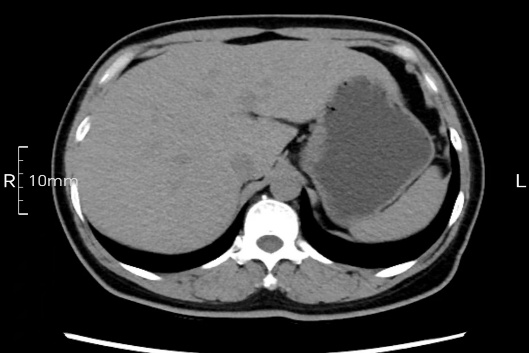

看看下面三幅便知遵醫(yī)囑的重要性。

禁食但檢查前沒有喝飽,胃未能漲開,胃壁觀察效果不佳。